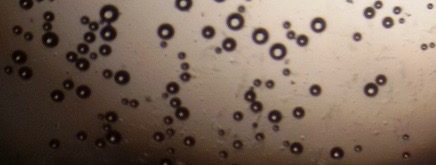

Proniosomes were transformed to noisome by hydrating with 10 ml distilled water at 37 °C and gentle agitation using vortex mixer (MaxiMix II, USA) for 5 min. The formed niosomes were sonicated twice for 30 seconds using sonicator (SONICS VCX 130, USA) [25]. The niosomal dispersion was put on a glass slide, and the formed vesicles were observed at a magnification of 1000x through an optical microscope. The formation of vesicles was observed using an optical microscope and photomicrographs were recorded [26].

The optical photographs of all reconstituted proniosomal formulae are shown in fig. (1-28). The photographs revealed that the formed niosomes are unilamellar vesicles with a spherical shape and smooth surface. The vesicles were insular and separate without aggregation or lumping. Apparently, proniosomal formulae containing span 40 and span 60 yielded vesicles of large numbers with well-identified outline and core which will affect the entrapment efficiency of loaded drug directly. However proniosomal formulae containing span 20 and span 80 produced small numbers of vesicles with a slightly different outline. This may be due to the high phase transition temperatures of both span 40 and span 60 which will cause the formation of a large number of stable niosomal vesicles. The phase transition temperatures for span 20, 40 and 60 are 16, 42 and 53 °C; respectively, however, span 80 possess the lowest phase transition temperature at 12 °C [35]. This explains why proniosomal formulae containing span 20 and span 80 produce small numbers of vesicles upon hydration.